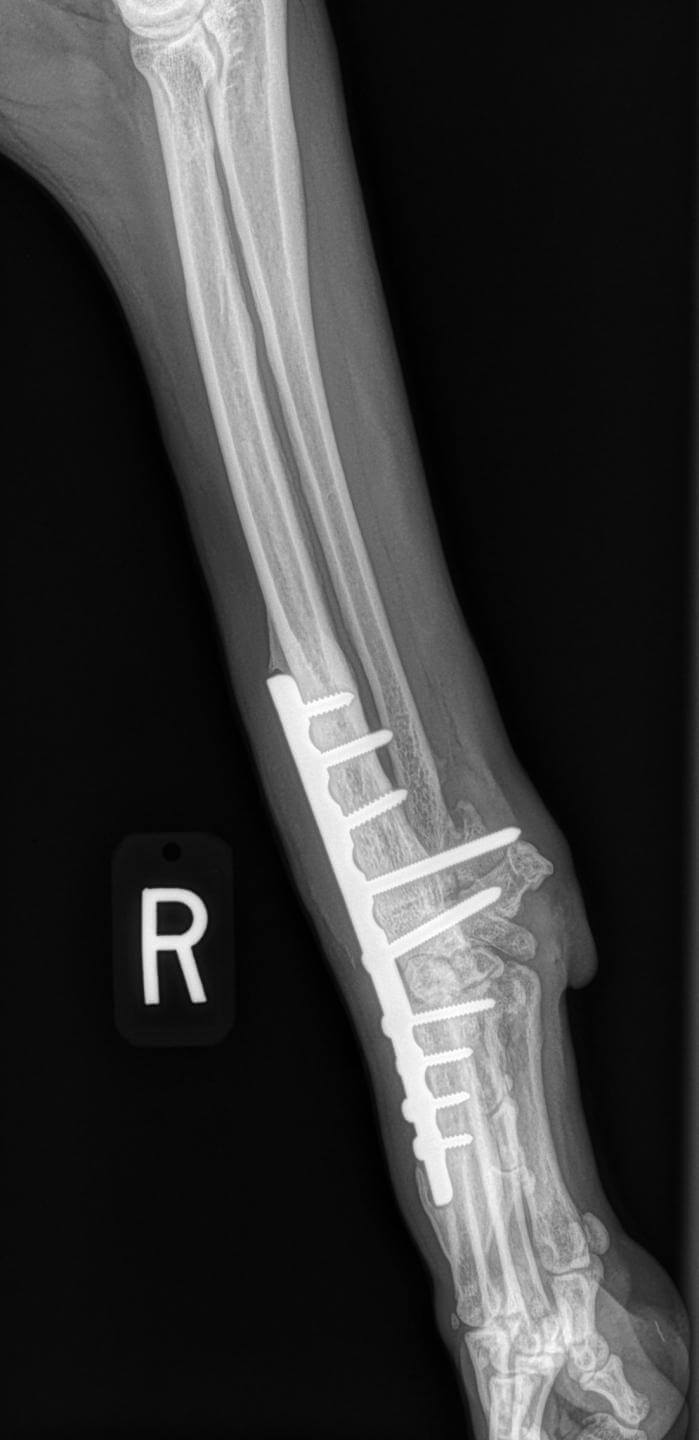

From criticalcaredvm.com

Carpal Arthrodesis in Pets Immobilizing the Wrist CriticalCareDVM Dog Carpal Joints If your dog is limping on her front. Carpal hyperextension is an abnormality of the wrist (carpus) that causes increased extension of the joint. This occurs when the carpus, which is the equivalent of the. Wrist) becomes unstable, causing it to drop toward the ground. As in humans, a dog’s bones and joints are subject to strains, sprains, dislocations, and. Dog Carpal Joints.